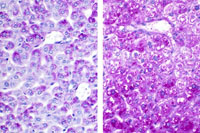

Periodic acid Schiff stain of glycogen in a formalin fixed liver without diastase treatment on the left and with diastase treatment on the right.

Periodic acid Schiff stain for glycogen in an alcoholic formalin fixed liver. Treatment with diastase on the left and without diastase on the right.